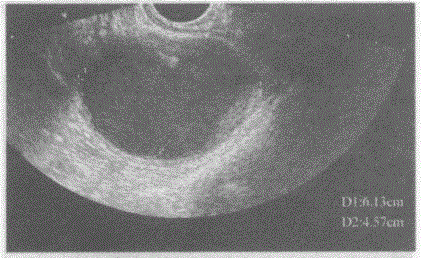

临床资料:女,27岁,自述月经期腹痛。临床物理检查:子宫右后方可扪及鸭蛋大肿块,压痛明显。超声综合描述:经阴道扫查左附件区可见6.6cm×6.1c...

问题 临床资料:女,27岁,自述月经期腹痛。 临床物理检查:子宫右后方可扪及鸭蛋大肿块,压痛明显。 超声综合描述:经阴道扫查左附件区可见6.6cm×6.1cm×4.6cm无回声区,边界清晰,形态规则,囊壁较厚,内透声不清亮,可见较密中强回声光点及光团浮动,CDFI:其内未见动静脉血流信号。 超声提示:

选项 A.左卵巢巧克力囊肿 B.左卵巢黄体囊肿 C.左输卵管积液 D.盆腔包裹性积液

答案 A